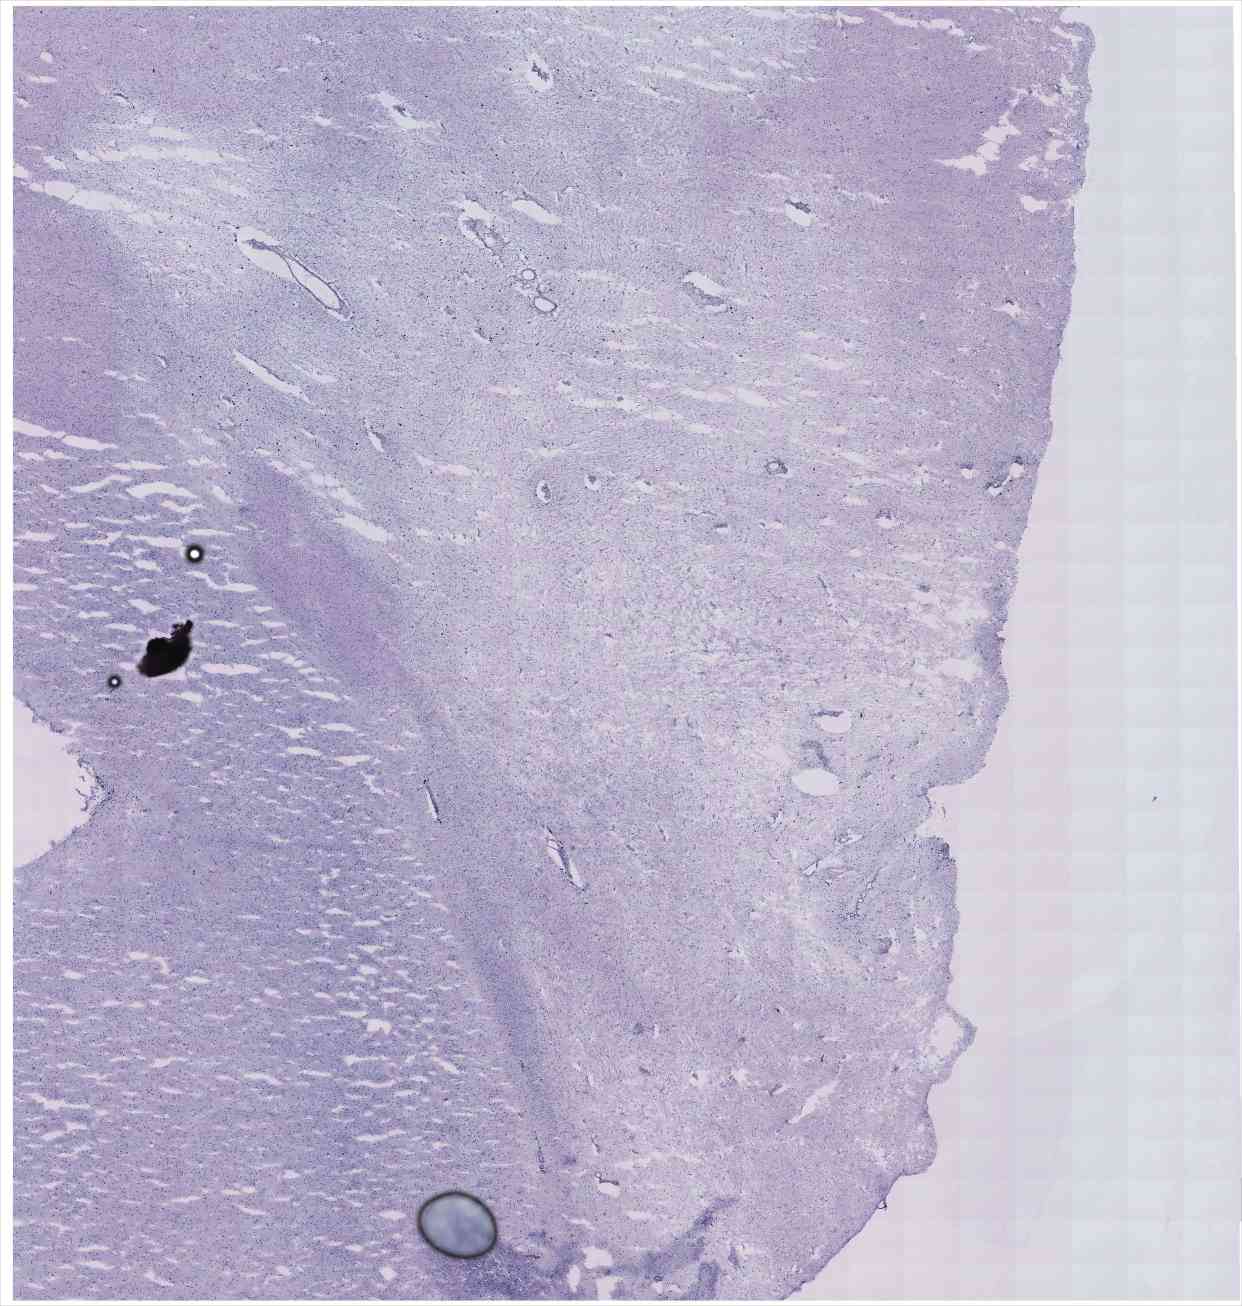

Chip 042 Well E2